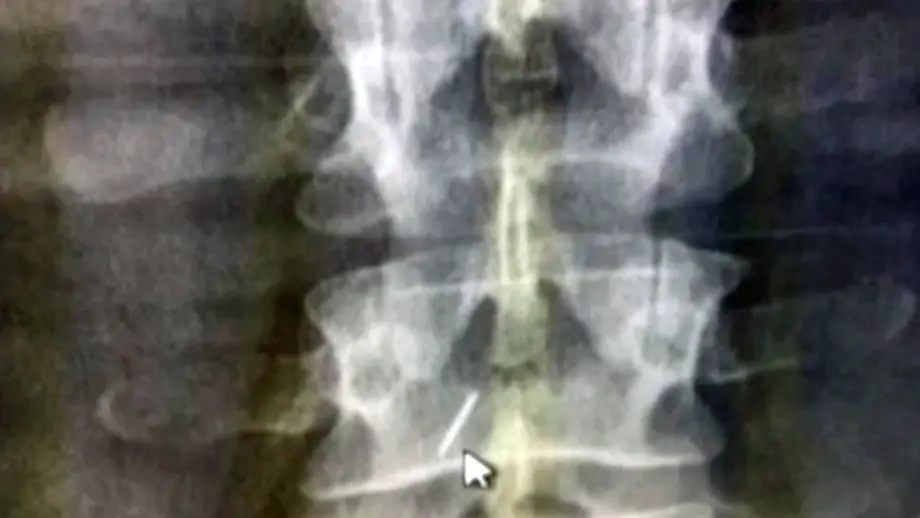

Von Ärzten dort "vergessen"?Frau läuft wohl 18 Jahre mit Nadel in Wirbelsäule herum

08.10.2020, 18:25 Uhr18 Jahre nach der Geburt ihres Kindes hat Giovanna Ippolito einen schlimmen Verdacht: Ärzte vergaßen oder übersahen damals womöglich eine Nadel. Die steckt nun in ihrem Rücken und bereitet ihr schlimme Schmerzen.